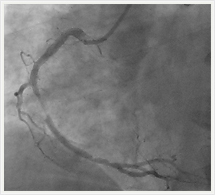

画像紹介(心臓血管編)

冠動脈形成術(PCI)治療は、身体に大きな傷をつけることなく、 狭くなった冠動脈の血管を内側から拡げるために行う低侵襲的な治療法です。